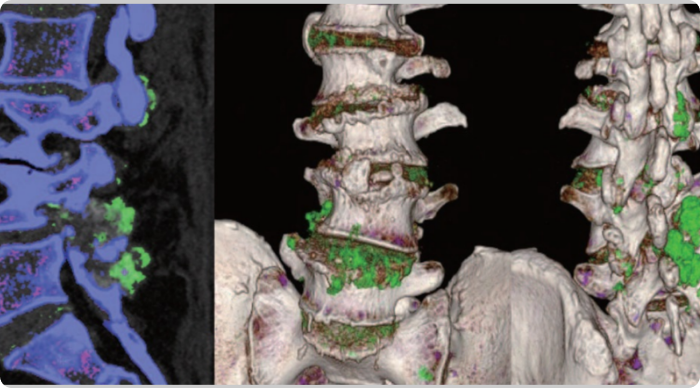

DECT scans of lower spine showing tophaceous deposits

Sagittal DECT and 3-dimensional DECT reconstruction show extensive tophaceous deposits (in green) in L1/2, L2/3, L3/4, and L4/5 lumbar discs, and also L2-L3 and L4-L5 facet joints.2

Adapted from Lu H, et al. Medicine (Baltimore). 2017;96:e7670.

KRYSTEXXA has not been studied to reverse damage to the spine or any of the body's organ.

DECT, dual-energy computed tomography.

CT, computed tomography.

DECT scans of lumbar spine showing tophaceous deposits

Sagittal mixed 120-kVp equivalent images of lumbar spine obtained with dual-energy CT demonstrate an intermediate-attenuation mass in the L5-S1 facet joint with bony erosions and narrowing of the neural foramen (arrow, left). Dual-energy material labeling color map overlay shows monosodium urate (green) and bone (blue and pink). Note the monosodium urate crystals crowding the left neural foramen (arrow, right).3

Adapted from Gibney B, et al. Radiology. 2020;296:276.

KRYSTEXXA has not been studied to reverse damage to the spine or any of the body's organs.